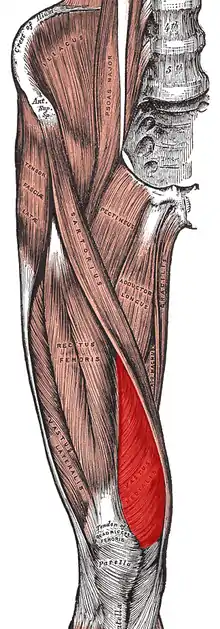

| Diagram of the bones of the lower extremity. Rough distribution of areas affected by PFPS highlighted in red: patella and distal femur. | |